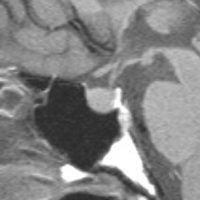

典型的なMRIの画像です

下垂体腺腫のMRIです。両側の視野障害(両耳側半盲)のために手術を受けた患者さんのものです。この腫瘍は非機能性腺腫といってホルモンを出さない腫瘍でした。少し大きめでしたが全部取れて視野の障害はよくなりました。

左の2枚はガドリニウム造影剤を使って写したもので腫瘍の形がよくわかります。右の1枚はT2強調画像と言います。MRIでは撮影の仕方によって見え方が違います。